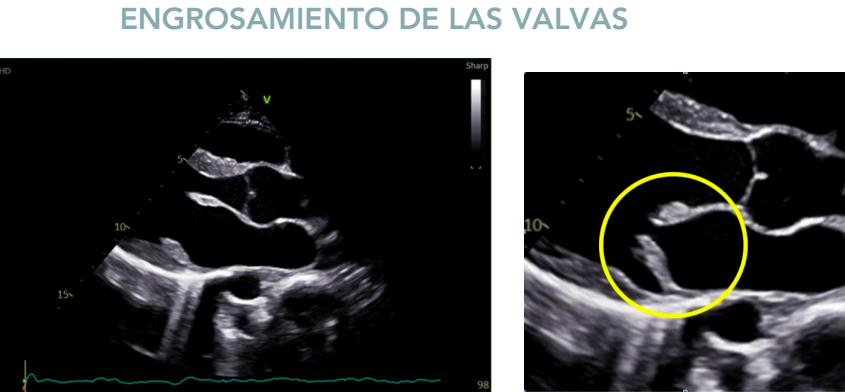

- Engrosamiento y prolapso valvular.

Engrosamiento de las valvulas